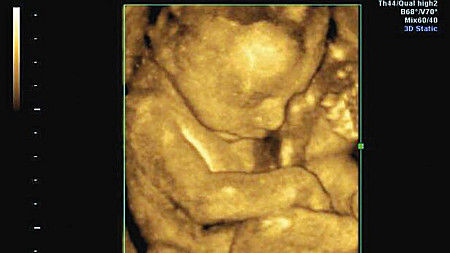

– To nie był łatwy czas. Miałam robione wiele badań i okazało się, że moje serce jest wydolne tylko w trzydziestu procentach. Lekarze mówili mi, że nie przeżyję ciąży, że wydolność będzie wciąż spadać, że może pęknąć mi aorta. Straszyli mnie także, że dziecko będzie niedotlenione. Reasumując, na całą sytuację mieli tylko jedną radę – „terminacja ciąży” – mówi kobieta.

– Czułam się przez całe 9 miesięcy bardzo dobrze. Urodziłam Nikolę przez cięcie cesarskie. Okazało się, że także ona jest zdrowa. Dziś córka ma pięć miesięcy, a ja patrząc na nią, czasem zastanawiam się, co byśmy narobili, gdybyśmy pozwolili na „terminację ciąży”. Kocham moją córkę. Wszystkim kobietom, które przeżywają dylematy, jakie miałam kiedyś, powiedziałabym jedno: „Zaryzykujcie! Lekarze nie wiedzą wszystkiego. Ponad nimi jest jeszcze Ktoś, kto nami się opiekuje”. Kiedy byłam w tak trudnej sytuacji, modliliśmy się dużo, odprawiane były Msze św. Byliśmy z prośbą w sanktuarium Bożego Miłosierdzia i na Krzeptówkach. Żyję i moja córka także – kończy swoje świadectwo pani Liliana z Małopolski.